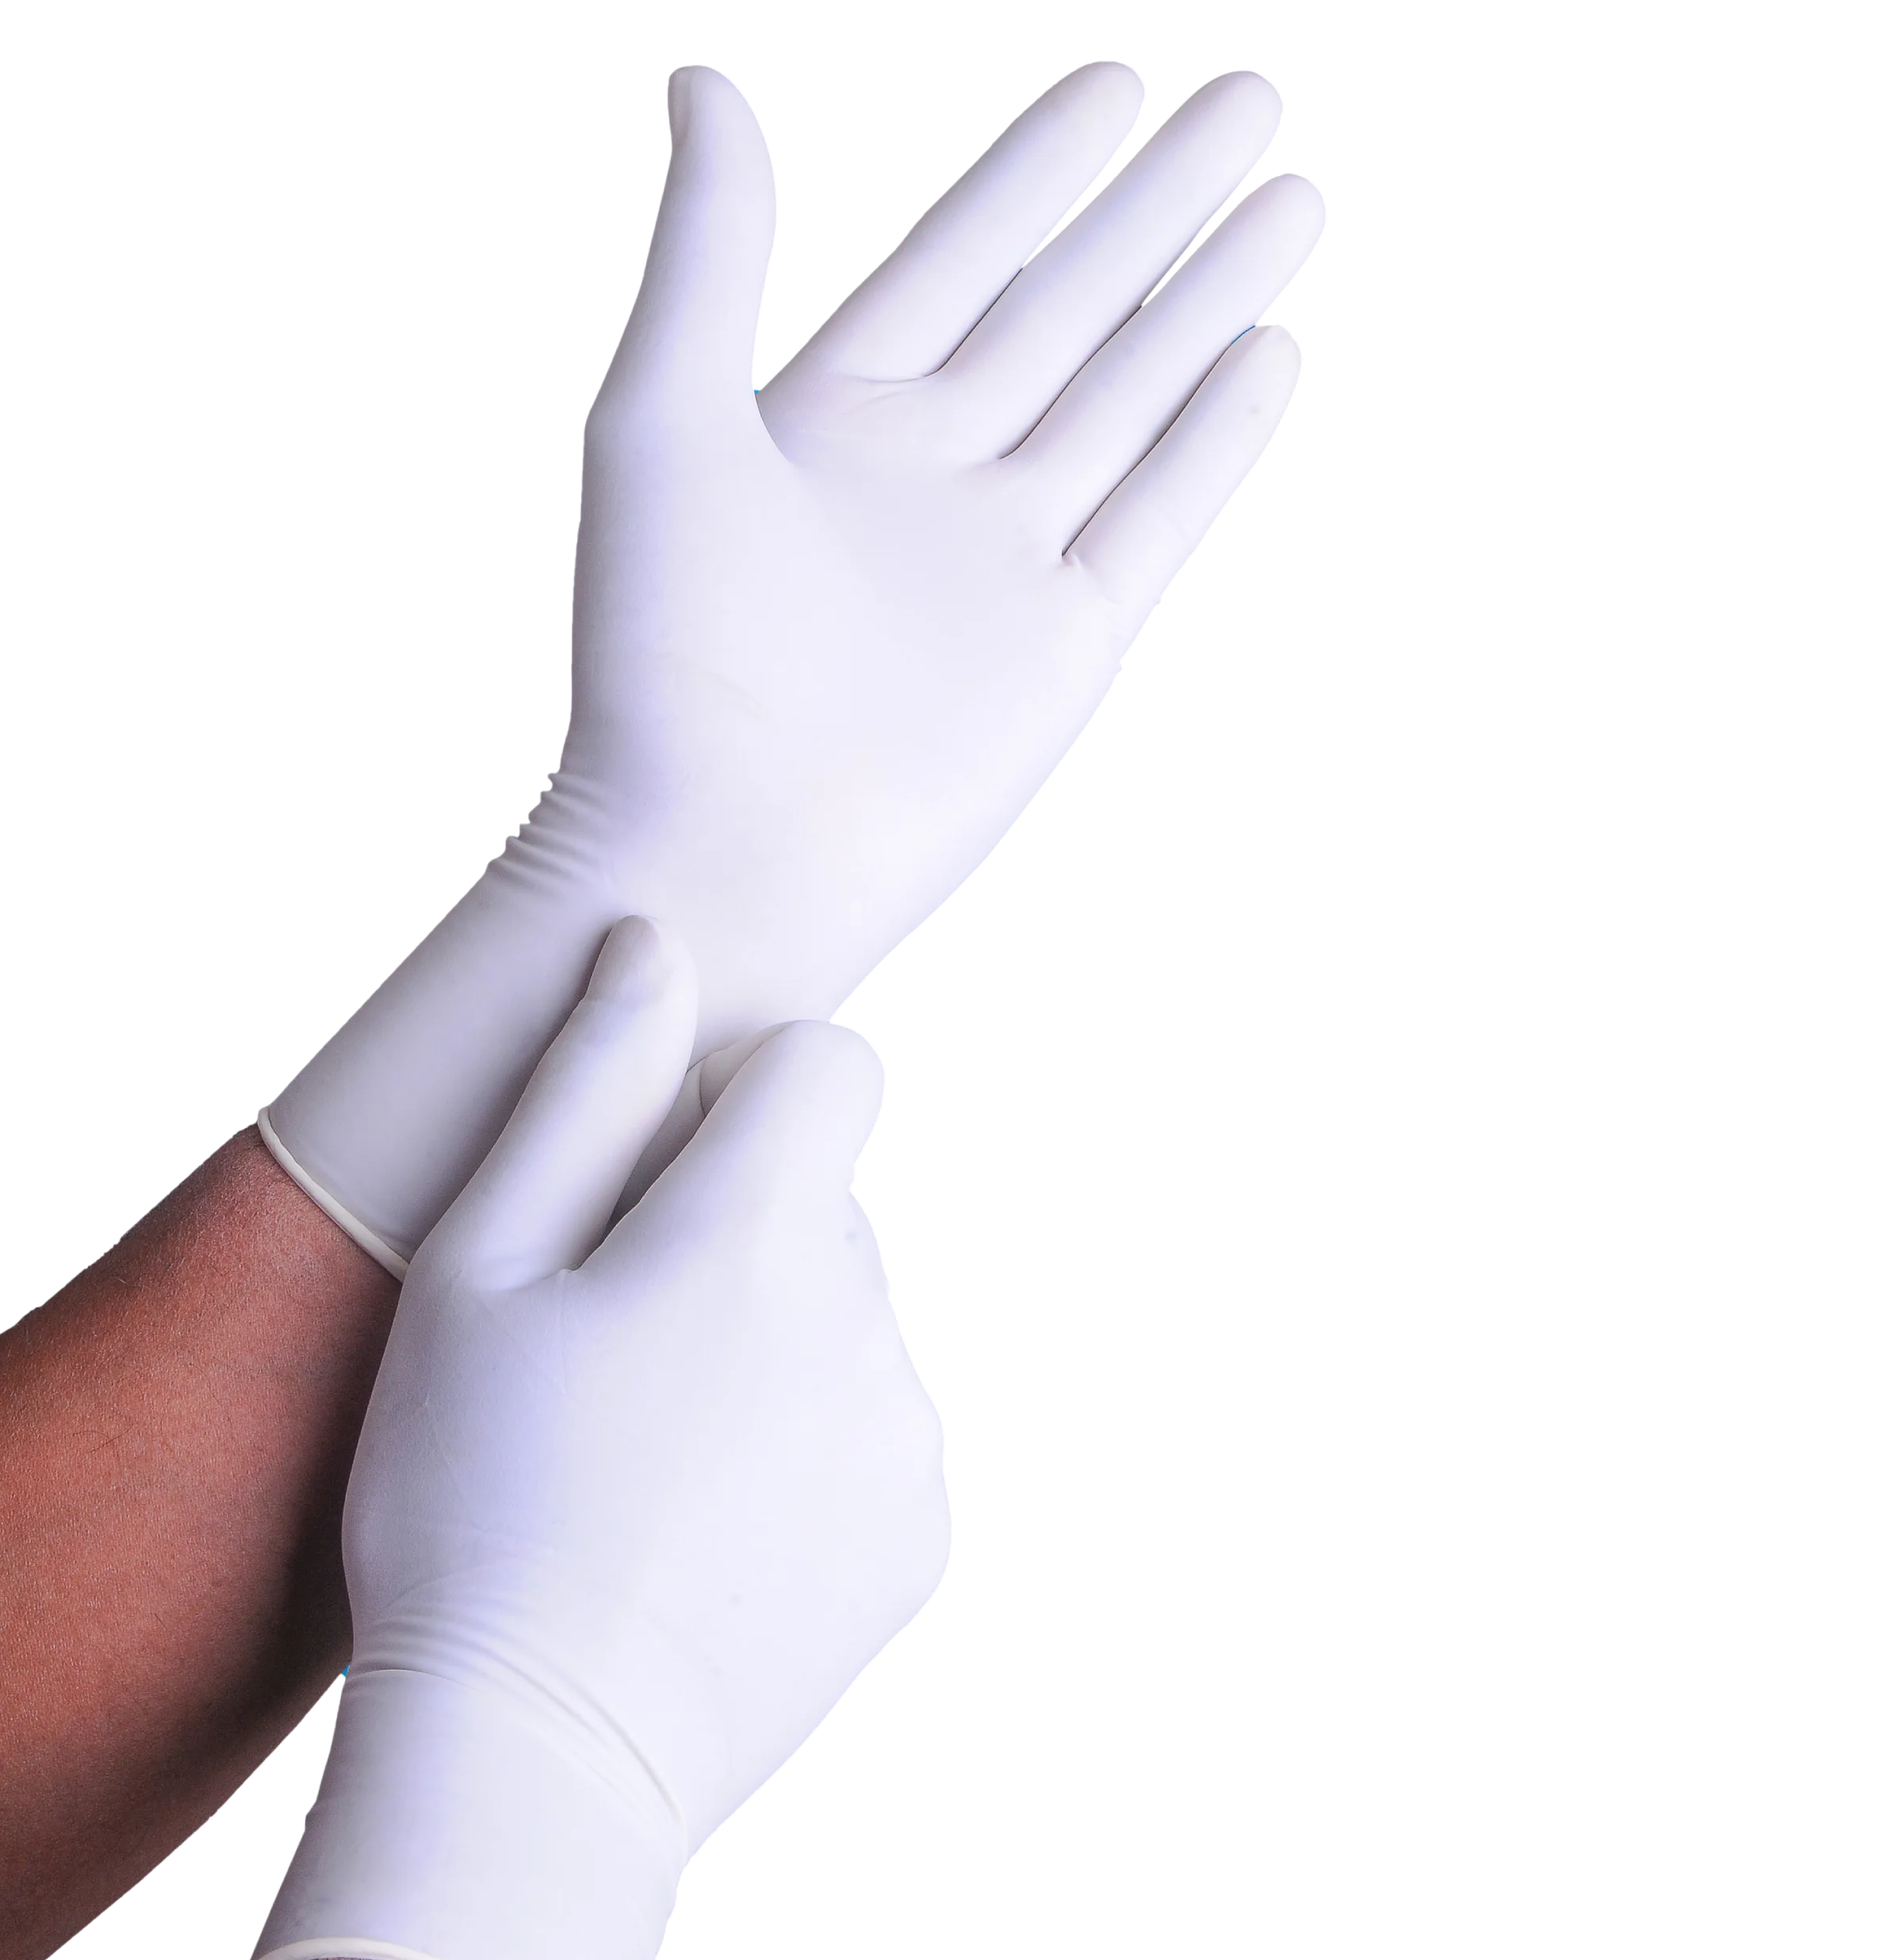

Surgical Gloves

Surgishield Surgical Gloves

Disposable Surgical Gloves

Surgi Shield Pvt Ltd. – a wide range of latex gloves. A well-known Kochi, Kerala-based producer, exporter, and supplier of premium medical gloves. As a customer-focused business, providing our esteemed clients with exceptional service and customized solutions is our top priority.

Made from Natural Rubber Latex

Anatomically Shaped Curved Fingers

Micro Roughened, Non-Slip Surface

Sterilized by Ethylene Oxide